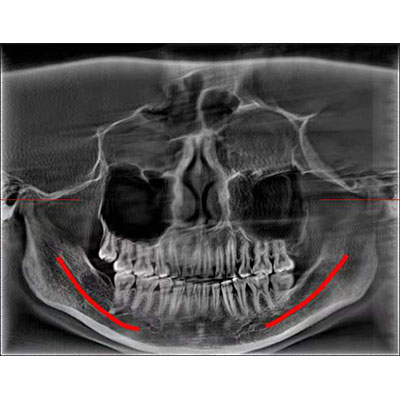

通過三維容積影像,提取高清口腔全景影像。